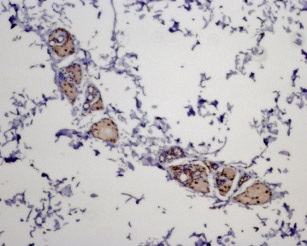

Expression of MC5R in rat skinImmunohistochemical staining of paraffin embedded rat skin section using Anti-MC5 Receptor Antibody (#AMR-025), (1:100). MC5R staining is present in sebaceous glands. Hematoxilin is used as the counterstain.